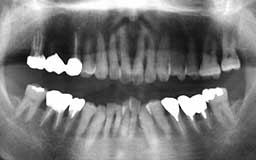

★ Pさん 52歳

年齢層をもう少し下げてみましょう。Pさんは来院時が52歳で、親知らずを除く喪失歯が

1本もなく健全そうにみえました。Oさん同様治療終了後の数年間にブランクがありました。

今から14年前の来院時にはメインテナンスを行うことの大切さがかなりはっきりわかってい

ましたので、それまでの経過を踏まえて少し強引にメインテナンスを勧めました。それ以降

はほとんど途切れることなくメインテナンスを継続されています。右の上顎第一大臼歯の1/3

だけ抜歯(ヘミセクション)していますので正確には現在残存歯数は27本と2/3ということ

になりますが、補綴(ほてつ)物も少なく10年後が楽しみな患者さんです。

| Pさん 初診時 52歳 男性 歯周疾患の進行傾向が随所に認められるが、年齢の割には比較的良好 |

Pさん 20年後 71歳 清掃状態は決して良好とはいえないが、20年間毎月メインテナンスを継続し良好な状態を保っている |